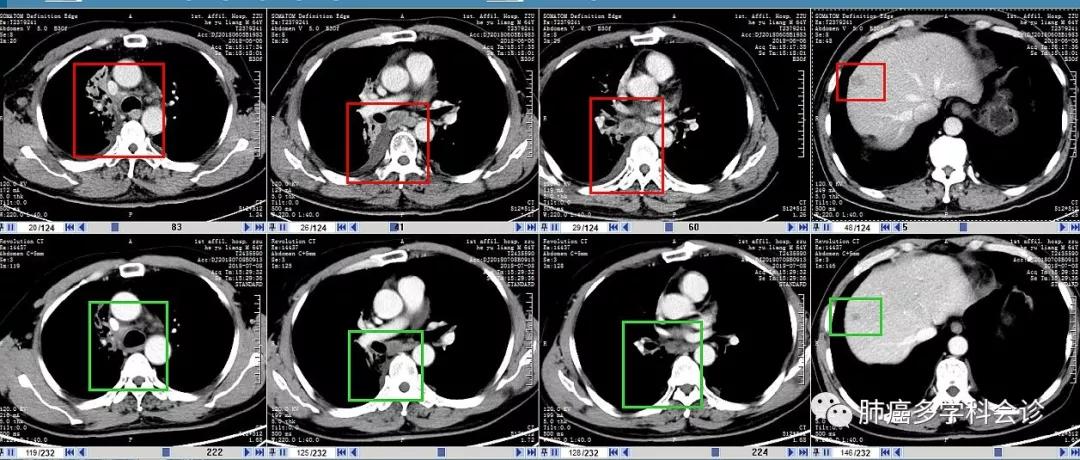

以下是2周期治疗前(每图上行,2018-06-06)和治疗后(每图下行,07-08)腋窝和纵隔转移淋巴结大小等的比较: